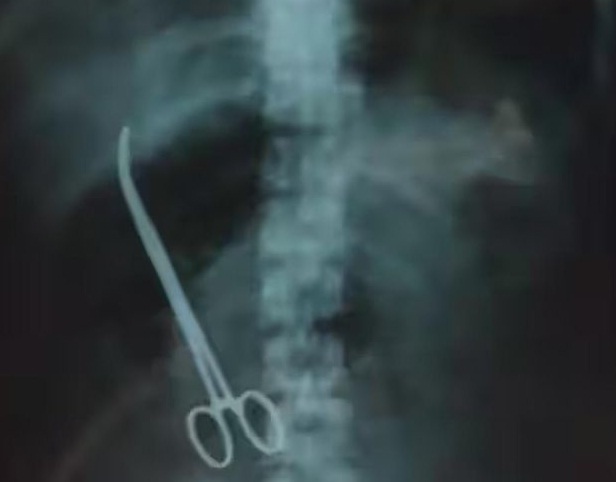

Various tests, including x-ray were conducted, at the Vijayawada Hospital and to their utter shock, the x-ray showed forceps in her stomach. However, the issue came to light when a hospital employee posted a photo of the x-ray on his social media accounts.

Artery forceps are used to control bleeding from blood vessels by clamping the artery. However, the doctor who performed the procedure forgot to remove the same.

The superintendent said a senior gynecologist had performed the cesarean but unfortunately artery forceps was left. He said when the woman came to the hospital on August 8, her condition was serious.